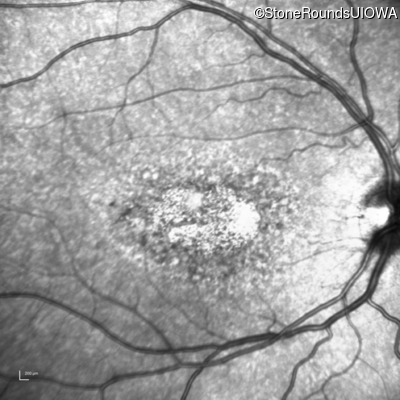

AR Stargardt Disease (IIA)

Age at visit: 29 years

This 29-year-old man had good vision until his early 20's. at which time he began to experience a slow reduction in his acuity. His driver's license was restricted at age 27.